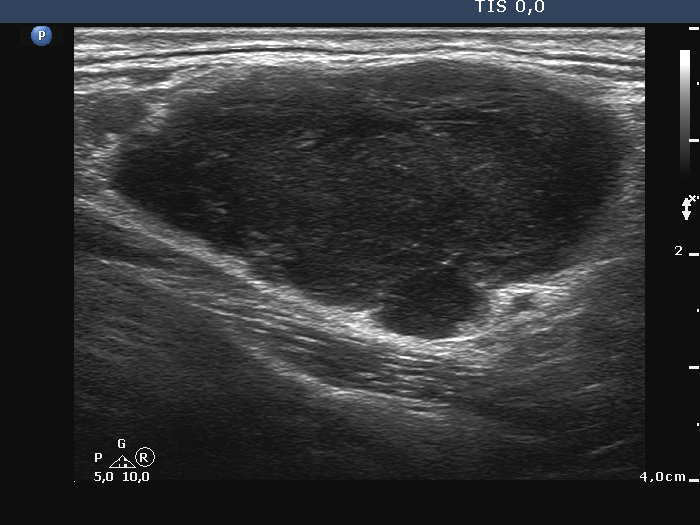

Left submandibular region, longitudinal scan. Note irregular, lobulated margins.